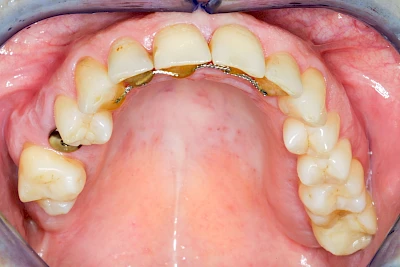

Neben rein implantat-getragenen zahnärztlichen Versorgungen werden bei herausnehmbaren Prothesen Implantate auch in Sinne einer "strategischen Pfeilervermehrung" ergänzend zu eigenen Zähnen zur Verankerung eines Zahnersatzes genutzt.